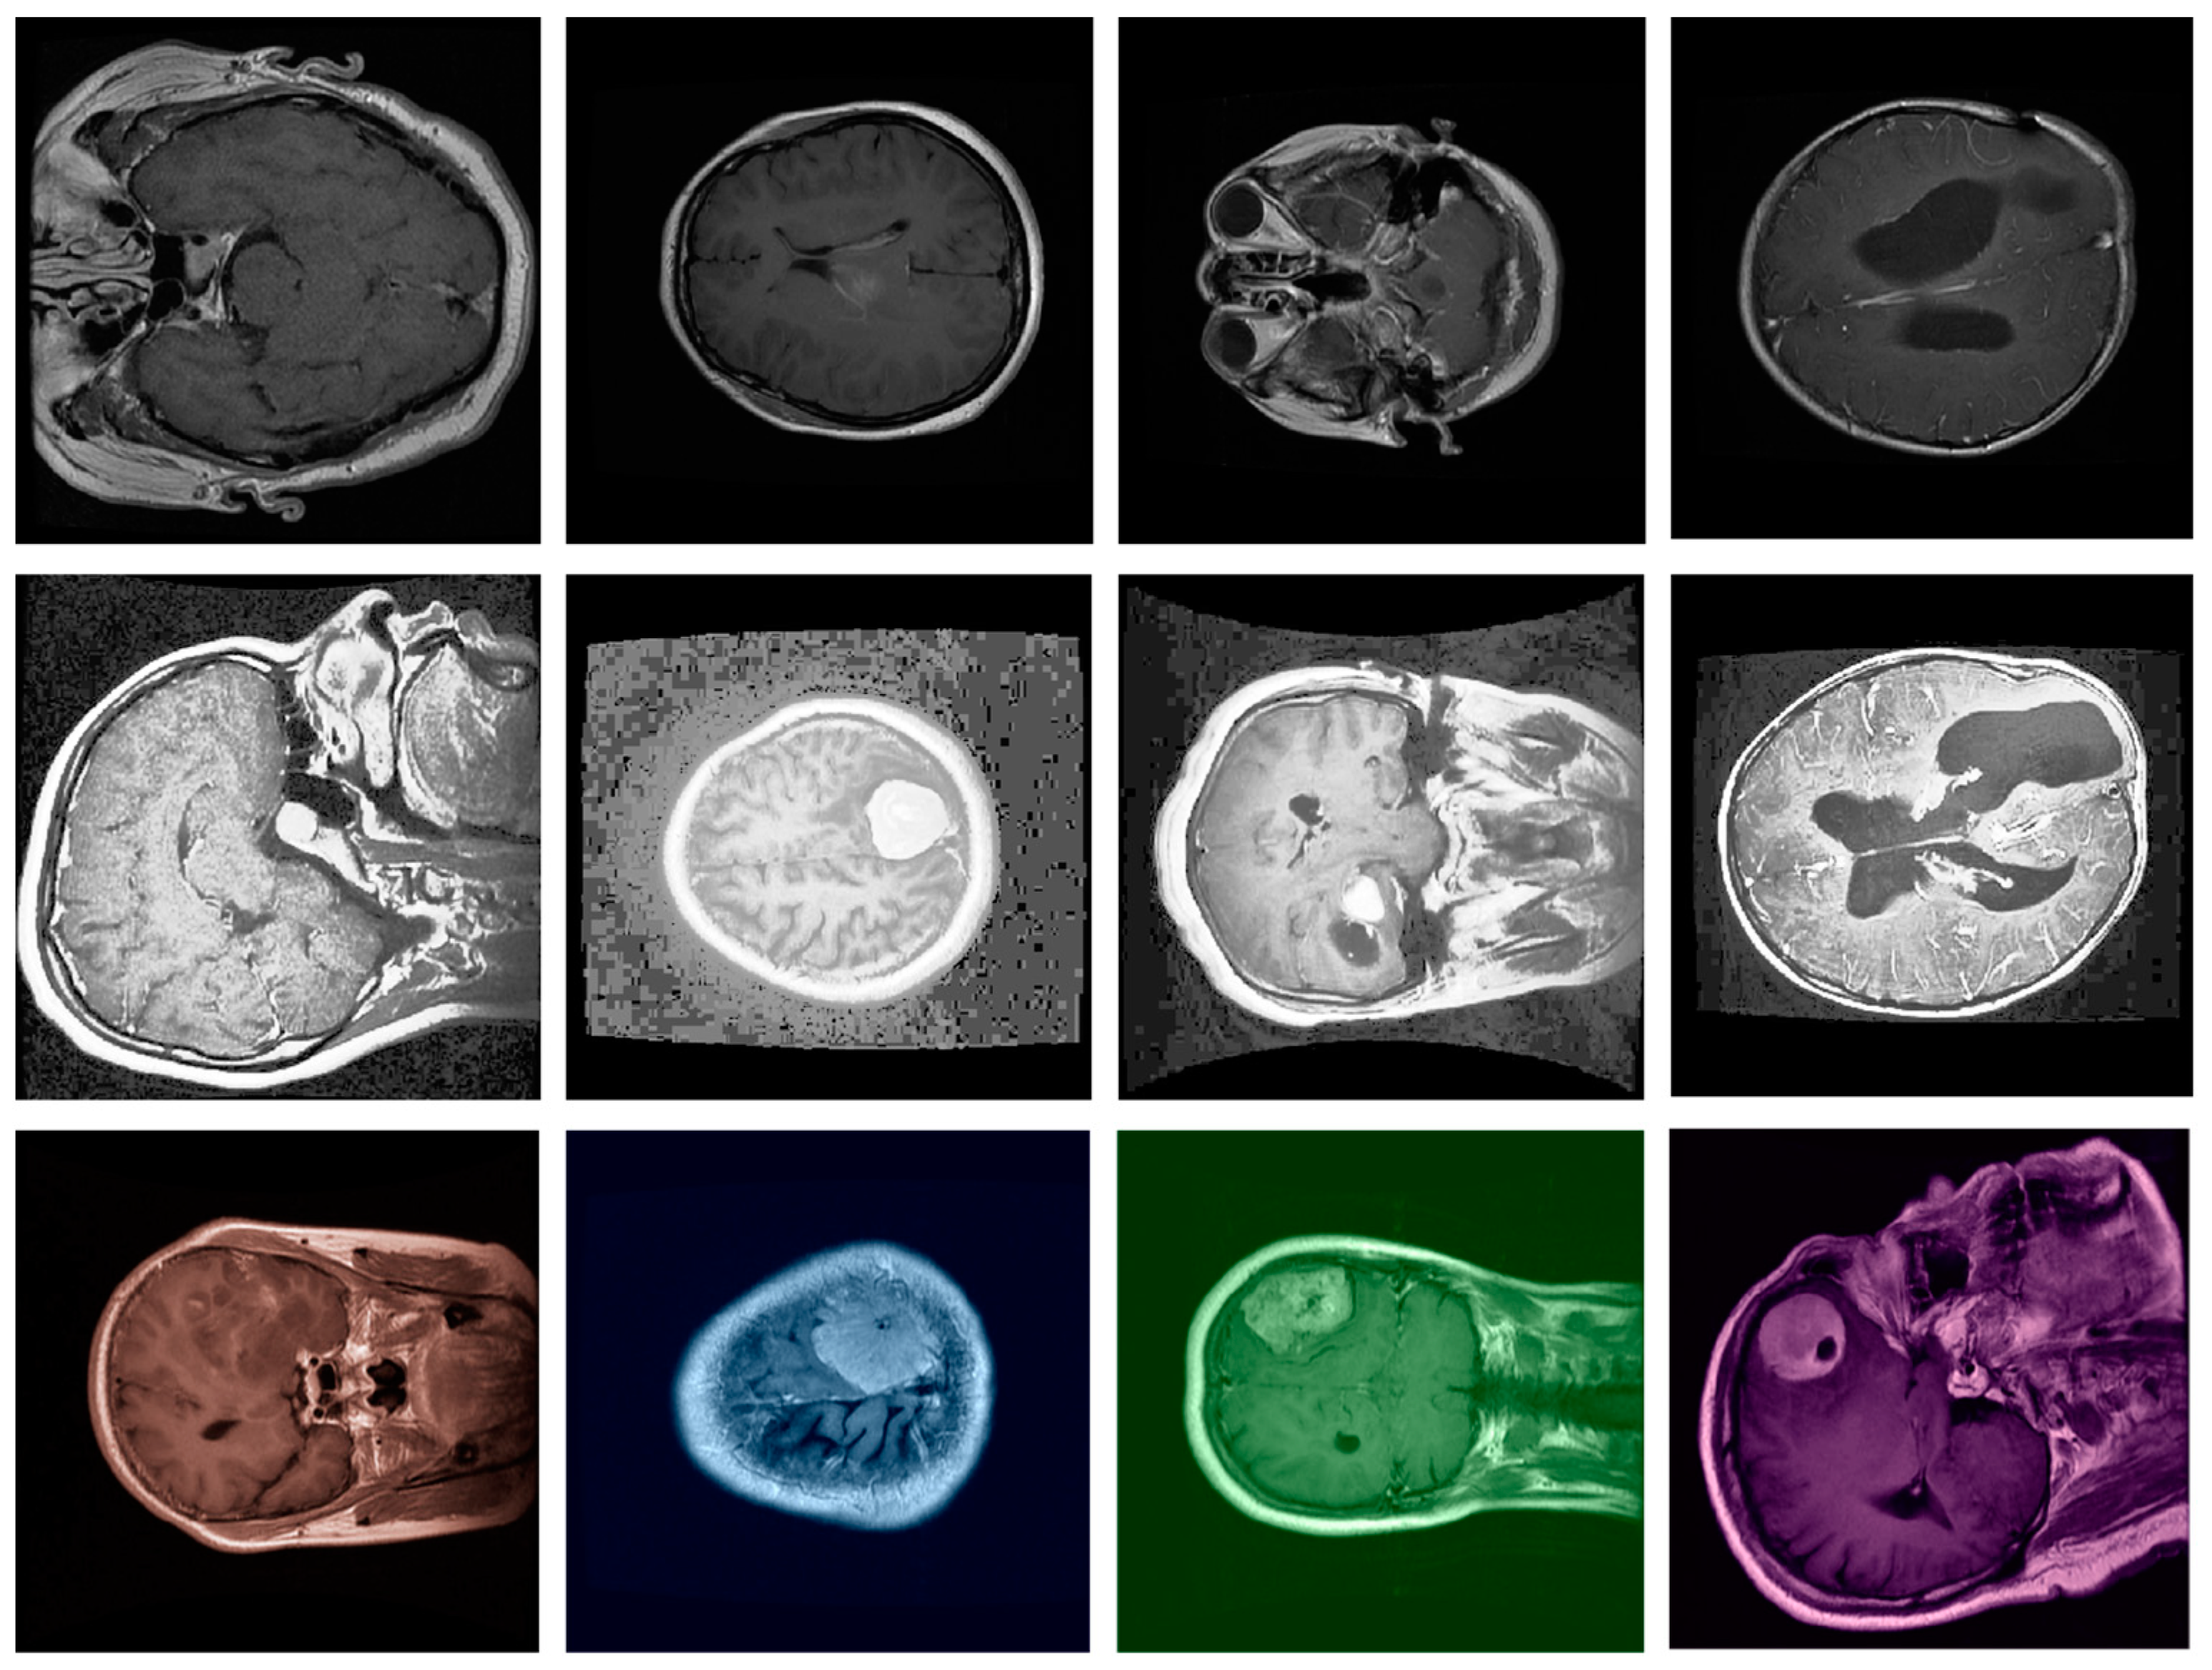

- Our model was evaluated on the Figshare dataset, which includes annotated MRI images of different brain tumor types: meningioma, glioma, and pituitary tumors. We provide a comprehensive comparison against leading segmentation models. Our results demonstrate that the proposed model achieves superior performance across metrics like accuracy, DSC, precision, and recall, confirming its robustness and reliability for clinical application.

4.1. The Dataset